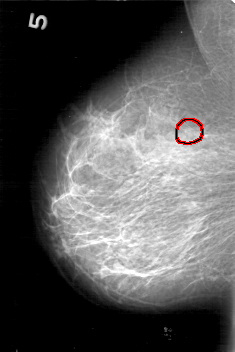

D_4167_1.RIGHT_MLO

FILE: D_4167_1.RIGHT_MLO.OVERLAY

TOTAL_ABNORMALITIES 1

ABNORMALITY 1

LESION_TYPE CALCIFICATION TYPE PUNCTATE-AMORPHOUS DISTRIBUTION CLUSTERED

ASSESSMENT 0

SUBTLETY 2

PATHOLOGY BENIGN

TOTAL_OUTLINES 1

BOUNDARY